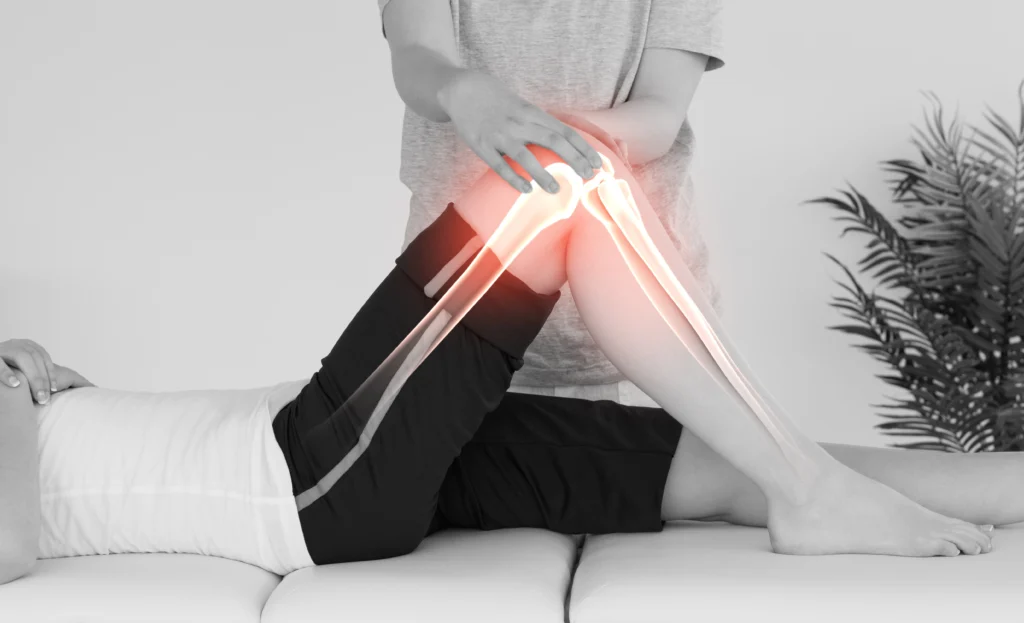

Effets musculo-squelettiques

Le massage agit directement sur les muscles sollicités par l’effort et favorise la récupération :

- Diminution de l’inflammation musculaire

- Modification de certaines protéines kinases

- Activation de gènes impliqués dans la régulation du phénomène inflammatoire

- Diminution de la production de cytokines inflammatoires (TNF-alpha, interleukine-6)

- Augmentation du nombre de mitochondries favorisant la cicatrisation des microlésions